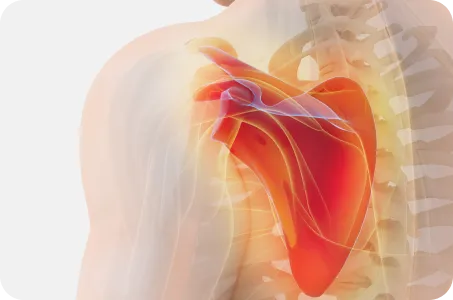

장기 치료 전략견갑골의 위치를 바로잡아, 어깨가 움직일 때 과도하게 사용되는 근육이 없도록 하는 원인 치료

[ 목 X 어깨 X 척추 X 골반 복합치료 ]

어깨로 내려가는 대부분의 신경은 목에서 출발, 경추의 불균형이 있는 경우 이를 교정하여 어깨로 내려가는 신경이 압박받지 않도록 공간 확보가 필수적

척추

굽은 등과 편평등은 견갑골의 위치를 틀어지게 만드는 주범으로 등뼈가 정상적인 커브를 이루고 있을 때 어깨가 가장 편하고 바른 자세가 됨

골반

어깨를 아래로 잡아주는 광배근, 중하부승모근은 골반이 틀어지거나, 양쪽 골반 높이가 다르면 어깨도 함께 틀어질 수 밖에 없음